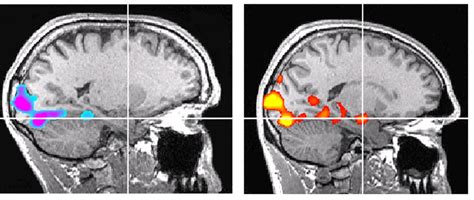

Individual- and Connectivity-Based Real-Time fMRI Neurofeedback to ...

mdpi.com